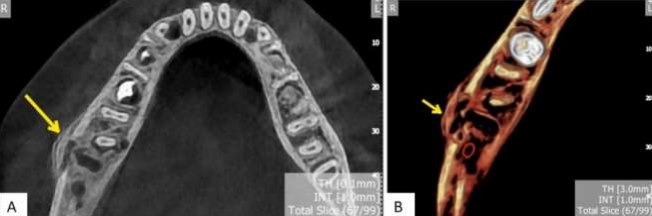

After the patient underwent additional cone beam computed tomography (CBCT) scans, the results showed many osteolytic lesions (moth-eaten) in the right mandible's ramus and body (Figure 2). It was noticed that the lesions ranged in definition from well-defined to ill-defined, and there was noticeable cortical duplication (onion peel appearance) (Figure 3).

Imaging tests are typically used to confirm the diagnosis of JMCO. Typical findings include mandibular enlargement and change in contour, lytic areas, enlargement of the mandibular nerve canal, partial destruction of the cortical-cancellous border, periosteal reaction, and a sclerotic, "ground glass appearance," or mixed radiopaque-radiolucent bone pattern [5]. Adjacent soft-tissue thickening is also common. The "ground glass" bone pattern frequently causes fibrous dysplasia (FD) to be considered in the differential diagnosis.